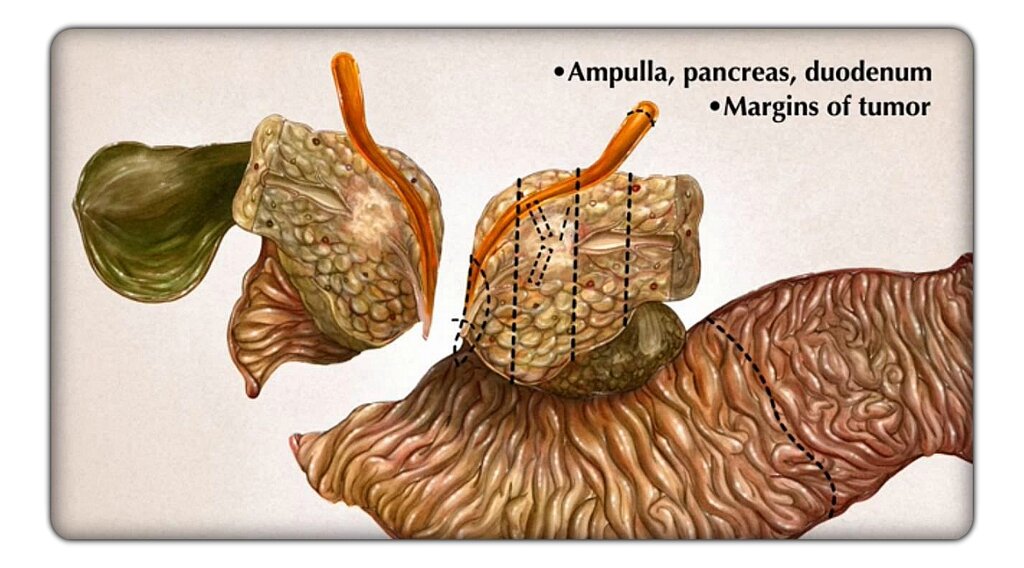

Фотографии медицинских исследований инсулиномы и синдрома Триады Уиппла